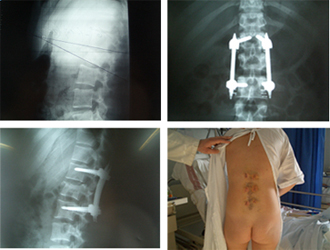

Imágenes de una artrodesis vertebral por técnica mínimanente invasiva donde puede apreciarse el abordaje de la zona intersomática para la colocación de espaciadores con injerto y de la instrumentación posterior.